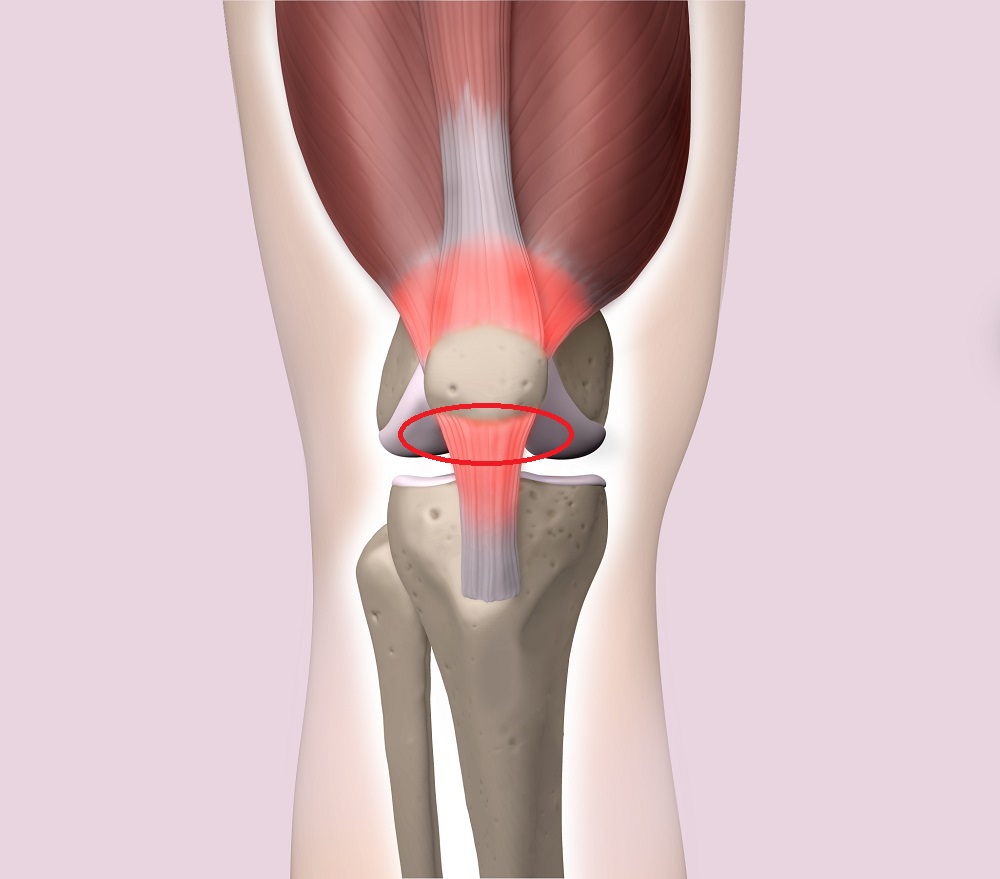

ジャンプやダッシュなどによる膝関節の屈伸動作を頻繁に、かつ長時間にわたって行う場合、膝の伸びる仕組み(大腿四頭筋が引っ張られることで膝蓋骨、膝蓋腱、脛骨粗面にまで牽引力が加わる)に過度な牽引力が繰り返し加わることで、膝蓋骨周辺に微細損傷を引き起こします(図)。病態は腱実質部に出血、浮腫、ムコイド変性(結合組織の粘液変性)、フィブリノイド変性(線維素様のものが組織に沈着して組織傷害や炎症を引き起こす)などの変化をきたし、微少断裂や、最重症例ではまれに完全断裂に至ります。

図:ジャンパー膝のメカニズム

膝の伸びる仕組み(大腿四頭筋が引っ張られることで膝蓋骨、膝蓋腱、脛骨粗面にまで牽引力が加わる)に過度な牽引力が繰り返し加わることで、膝蓋骨周辺に微細損傷を引き起こす